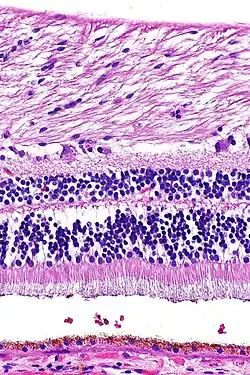

Histologisches Präparat einer Netzhaut

Das durch die Pupille einfallende Licht durchdringt Linse und Glaskörper als transparente Medien und passiert dann mehrere Schichten der Netzhaut, bevor es von den Photorezeptorzellen des Neuroepithels detektiert wird, die dem außen anliegenden Pigmentepithel zugewandt sind. Vom Glaskörper her zur Aderhaut hin, also bezogen auf das Auge von innen nach außen, zeigt die lichtempfindliche Netzhaut einen schichtartigen Aufbau aus Zellkörpern im Wechsel mit Zellfortsätzen. Hierbei lassen sich meist zehn Schichten unterscheiden, im Bereich der Sehgrube des Gelben Flecks sind einige seitwärts verlagert.